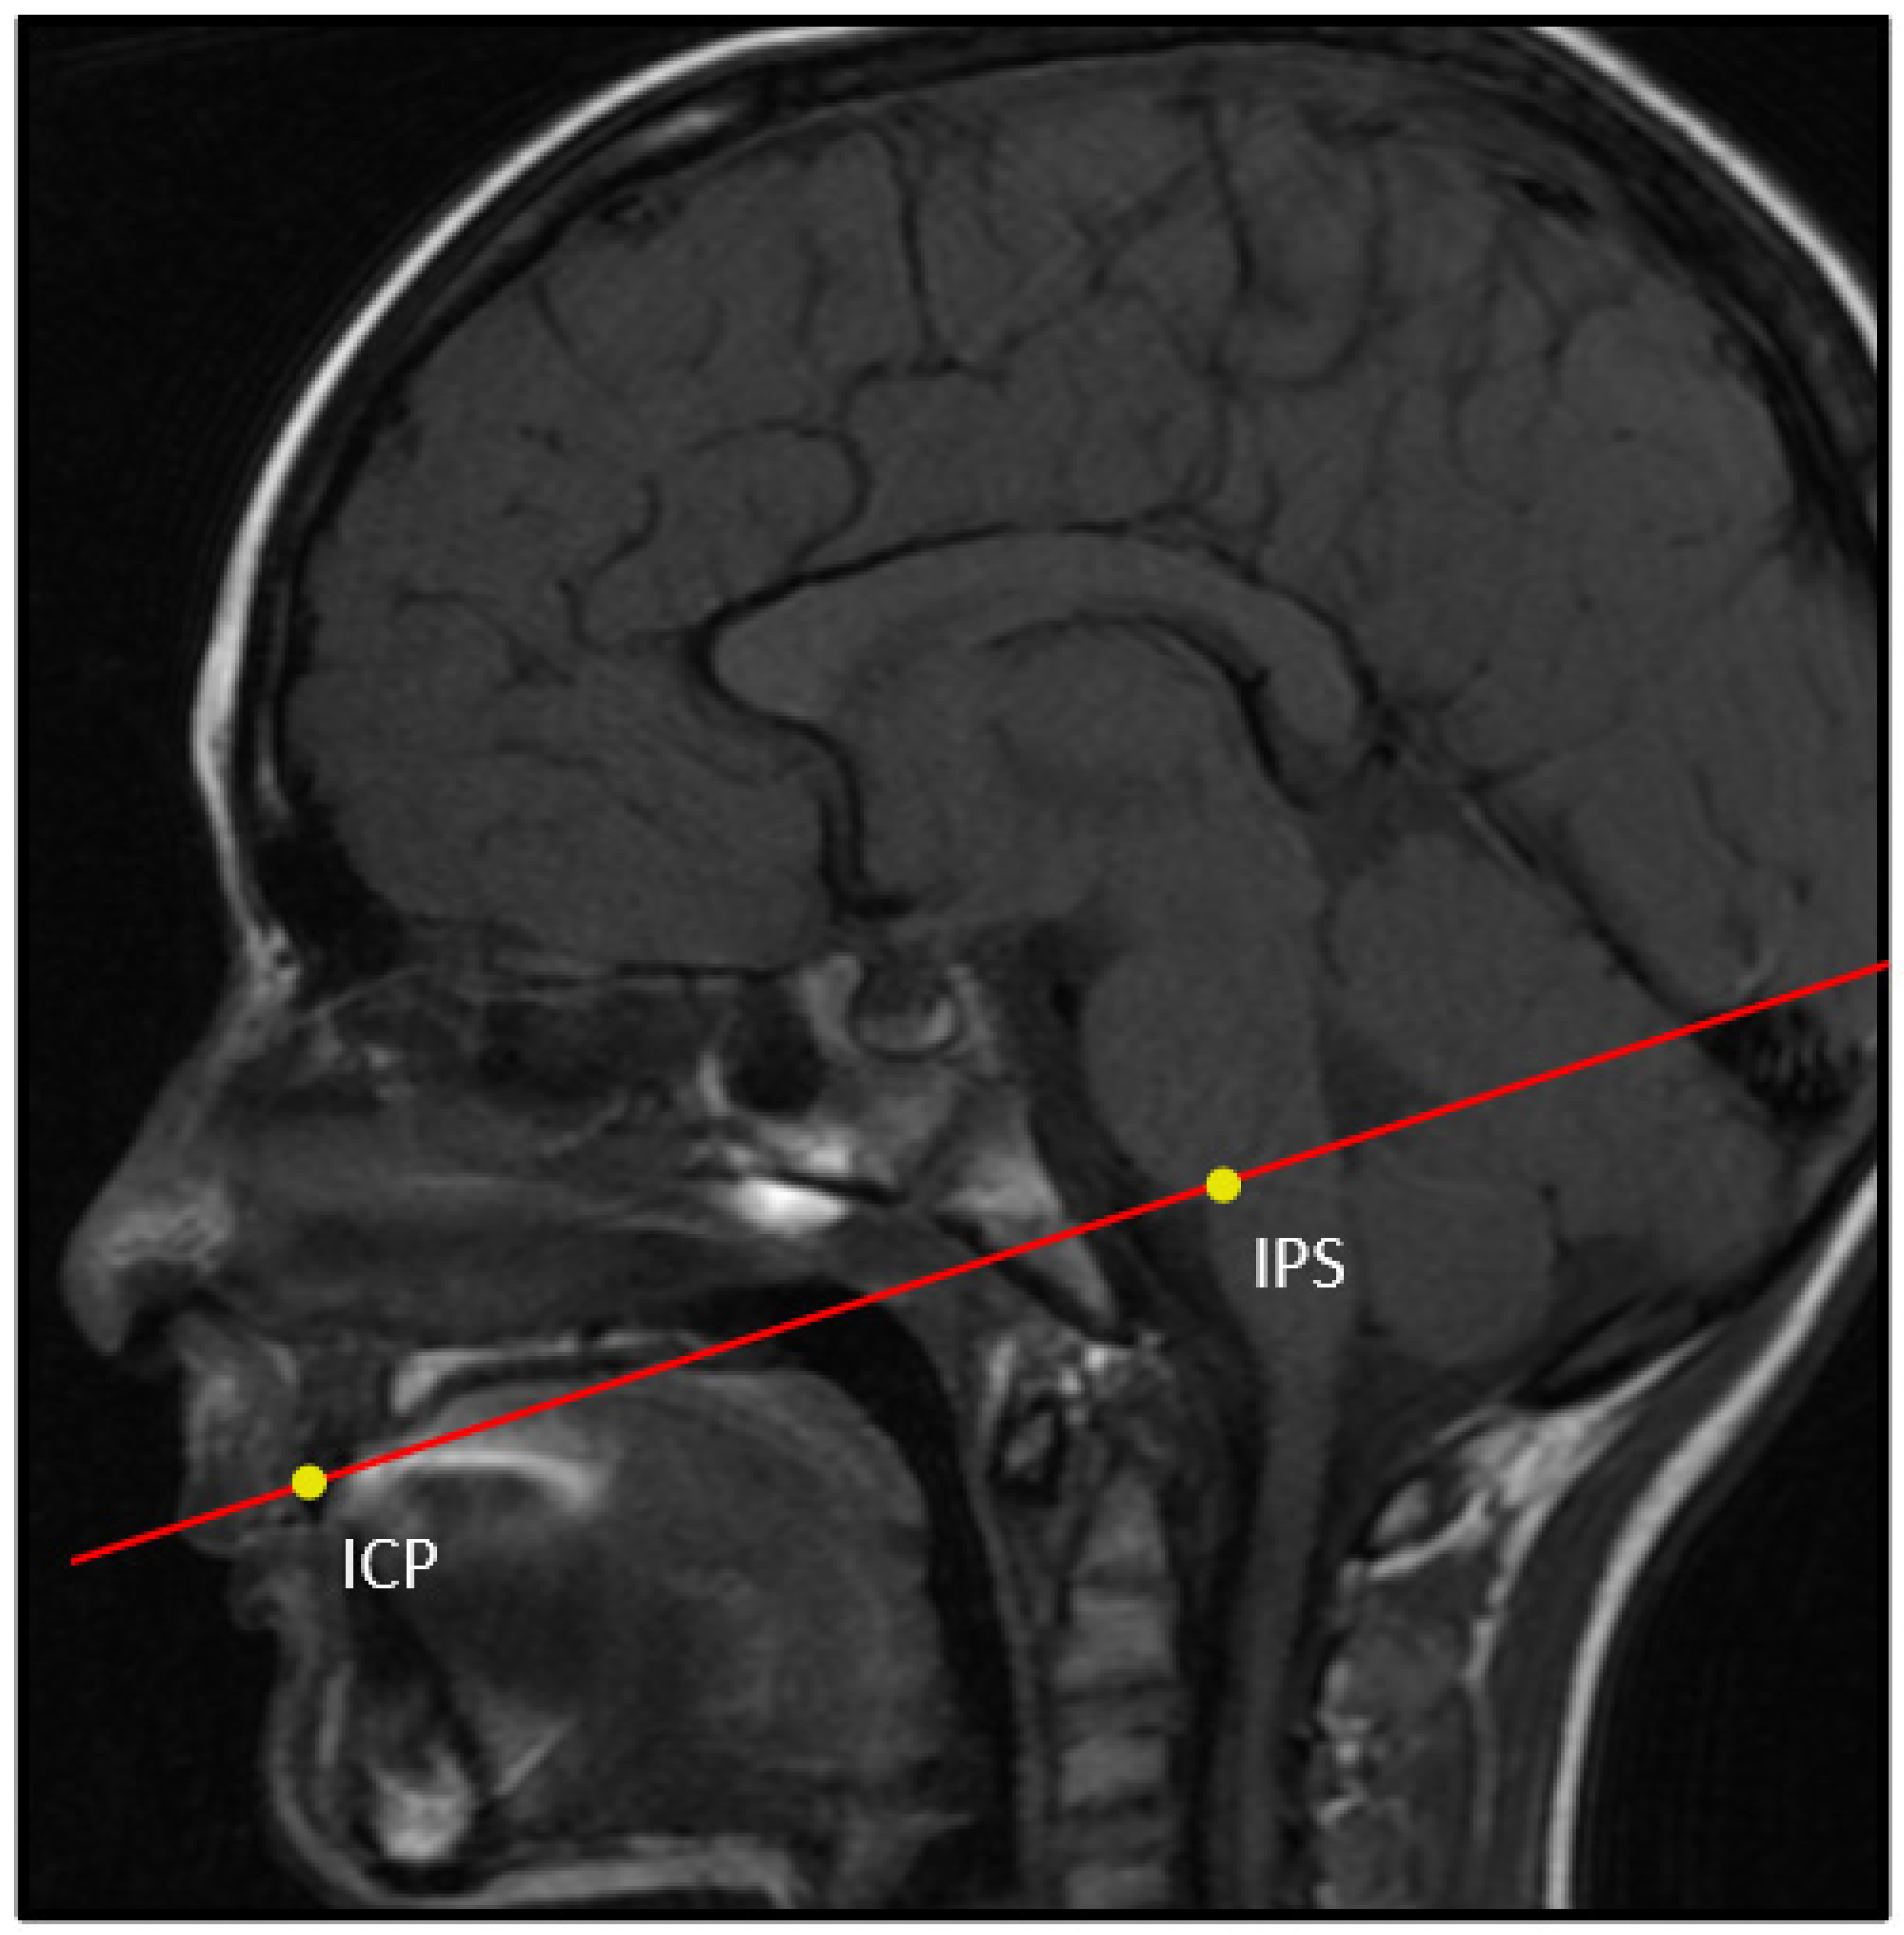

| Bone Landmark | Abbr. | Location | Definition | Description | Figure |

|---|---|---|---|---|---|

| Sphenobasion | SB | Midline | Midline of spheno-occipital synchondrosis | In a midsagittal plane, identify the clivus and place the landmark on the superior border of the clivus on the external surface in between the sphenoid and occipital bones; this is a cartilaginous plate in children. | Figure 2 |

| Basion (exo-basion) | BA | Midline | Midline of anterior foramen magnum | In a midsagittal plane, identify the most inferior–posterior point on the clivus. | Figure 2 |